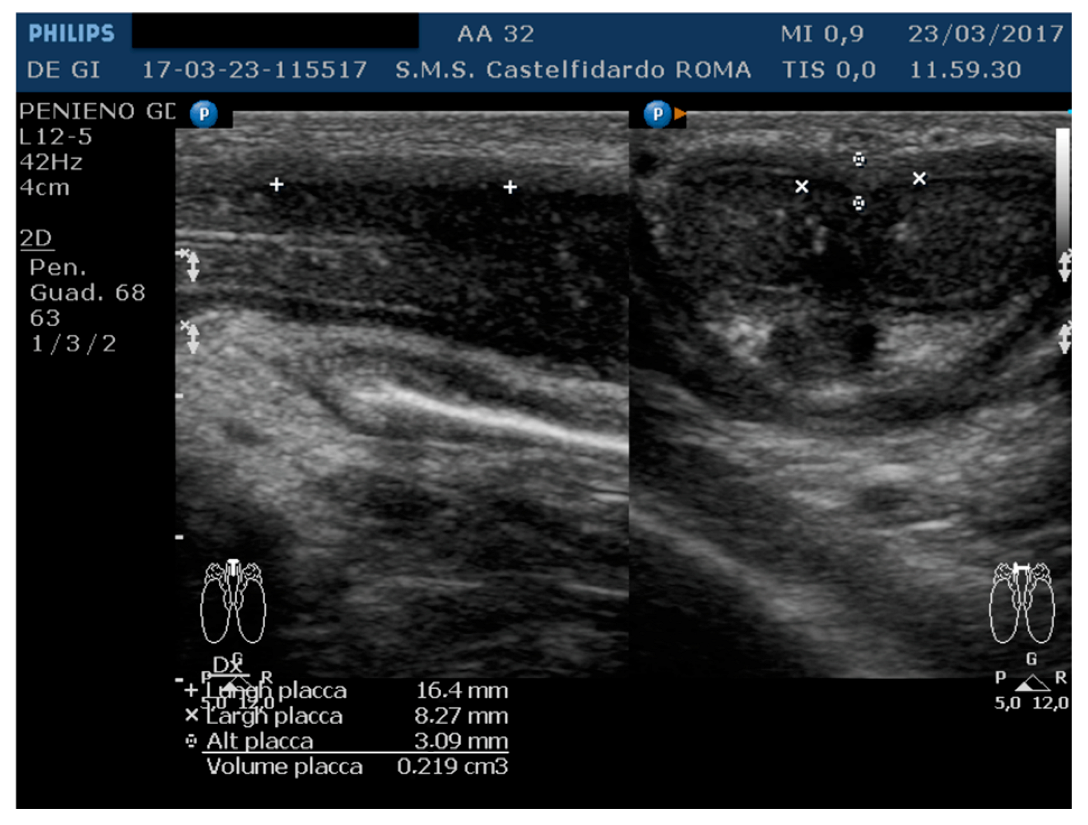

| 2 | 32 years | lichen sclerosus, chronic prostatitis | Proximal third | (A) 16.4 × 8.27 × 3.09 mm volume = 219 mm3 | (A) 10-degree left curvature | (A) score 3 | (A) score 26 | 2 years and 9 months | orally: Silymarin 400 mg + Ginkgo biloba 250 mg + Propolis 600 mg + Bilberry 160 mg + Vitamin E 800 IU/once a day, for 33 months. + topically: Propolis creme/twice a day/for 33 months. + peri-plaque penile injections: Pentoxifylline 100 mg (30 G needle) every 15 days for 6 months, and then monthly for 12 months, and then 1 injection every other month. for 12 months (total = 30 injections) |